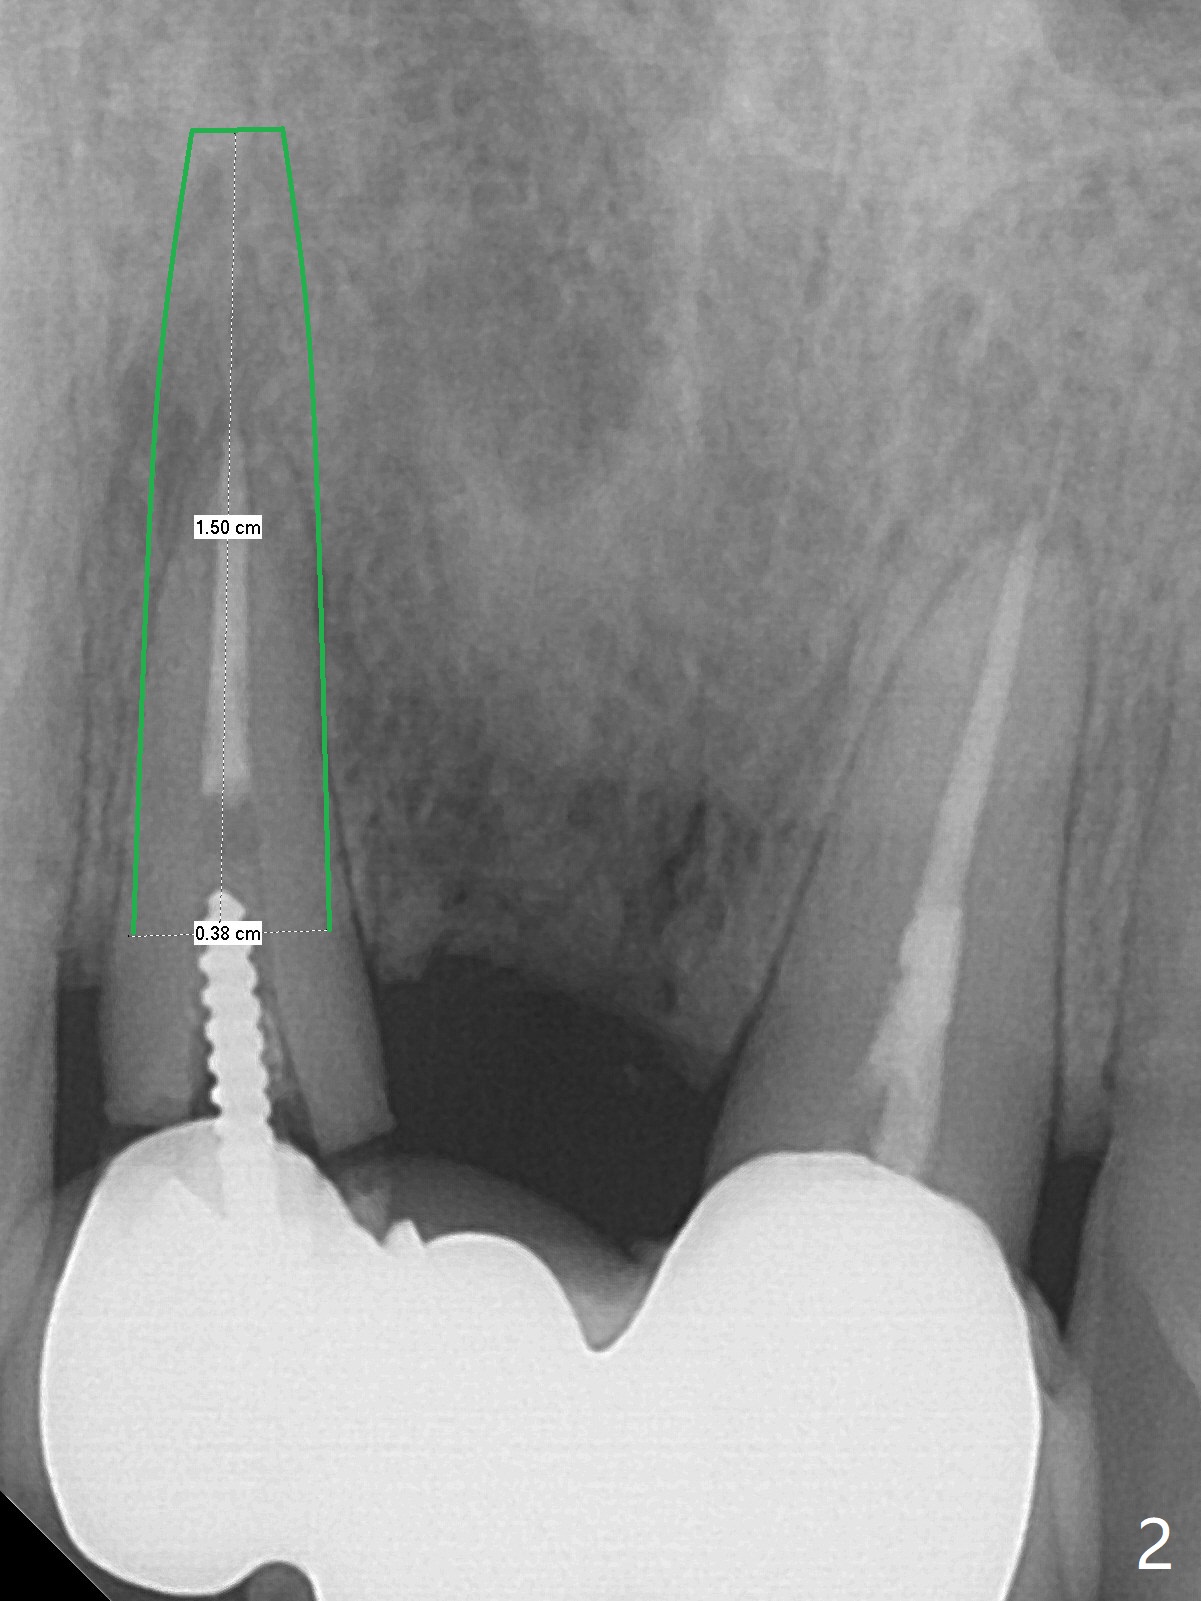

A 34-year-old woman requests fixing the failed anterior FPD (Fig.1). The edentulous alveolus looks thin; 1-piece implant may be indicated at most. A regular narrow 2-piece implant will be placed at the lateral incisor (Fig.2). CT is necessary for treatment planning. Impression has been taken for stent fabrication. 34岁女,一年半前来诊所(图一,二(侧切牙种植,做悬臂桥,暂时保留左上1牙冠)),希望修复右上门牙桥。现在终于要求立即做,基牙处牙龈红肿 (图三(今天做深洗)),牙桥颊侧移位(图四),侧切牙(7号牙)牙槽嵴也不是很宽,植入3.5毫米植体(两段式, IBS)还勉强(图五)。为了简化,避免悬臂桥,我还想在中切牙(8号牙)无牙处植入一段式2.5毫米植体(图六),适当做些牙槽嵴劈开(图六右上图:红线; from IBS cassette)。这周末徒手植入,她离开时应该有固定临时修复物。

Sequence of treatment: Section FPD between 8 and 9, photo of the narrow ridge of #8, incision, suture fixation of the flaps, ridge trimming with surgical handpiece/round diamond bur, confirmed by Tatum implant positioners (3 mm), 1.2 mm drill (8 mm deep), broken drill in place for PA later, ext #7, photos of curettes and granulation tissue removal instruments, 1.6 mm drill in the middle of the palatal slope, 1st intraop PA, #8 ridge split with IBS blade osteotome or thin surgical bur, subcrestal implant placement, fabricate temp especially for #8 before bone graft and suture to make sure subgingival margin and temp creating space for bone graft to make sure buccal and palatal bone thickness.

一段式植体似乎不美观,其实它适用于近中远中空间狭窄地方,如这个病例,而两段式植体显得太粗,没有空间形成牙龈乳头,况且容易以后导致植牙周围炎。即刻临时牙冠手术第一天就起到美观作用,术后三四个月中反复调整,为永久性牙冠奠定基础。以下手术步骤就是为了这个目的。在中切牙之间切断牙桥,为右上1狭窄牙槽嵴拍摄照片(颊侧,咬合面观),切口,铬羊肠缝线牵拉,外科车针去除尖端牙槽嵴直到后者宽度达到~ 3毫米,使用1.2毫米一段式钻头,8 毫米,插入一个已经折断同样大小车针作为定位;拔除侧切牙,拍摄各式各样刮匙和肉芽组织去除器械,用1.6毫米钻头在腭侧骨板钻洞,深度9毫米,拍摄术中第一张根尖片;在中切牙处使用片状骨凿稍做骨扩张,必要时旋转式扩大器,之后完成牙槽嵴下植体放置,侧切牙牙槽窝以及中切牙术野插入无絮棉布,做必要基台制备,使用成品临时牙冠制作两个分开牙冠,确保牙龈下边缘,取出棉布,植骨,放置PRF膜,插入临时牙冠,尤其是中切牙牙冠和骨粉将改善颊侧,腭侧(与图四箭头对比)饱满度,最后缝合,调整咬合。7,8号牙骨质密度分别为700和 500单位(图七,八)。